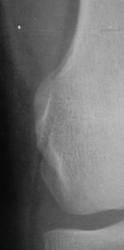

Травма. Пациент направлен на рентгенографию коленного сустава.

Пациент направлен на рентгенографию коленного сустава.

Определяется уплотнение кортикального слоя суставных поверхностей, заострение межмыщелковых возвышении, слабовыраженная краевая  костная деформация - по совокупности   тянет на ДОА I ст. Ну, а то, что на прицельной то это - игра теней - мое мнение.

Прицельных снимков не делали, это обычных два снимка на цифре.

ДФА 1

артроз пателло-феморального суставчика и лигаментоз крестовидных связок.